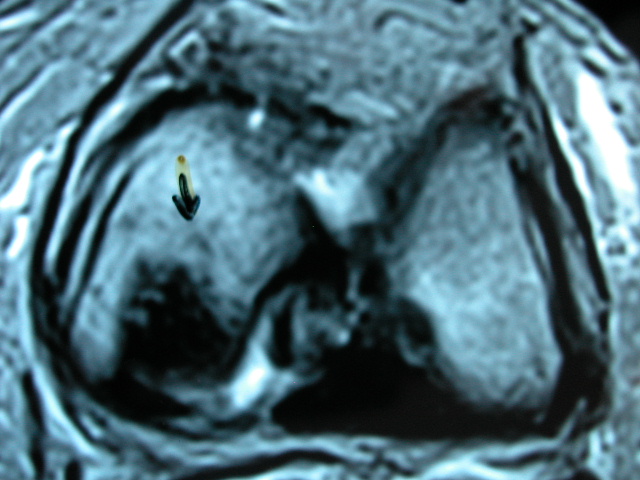

ACT Osteonecrosis de rodilla. RM.

ACT Osteonecrosis en la cúpula astragalina por afectación vascular. RM.